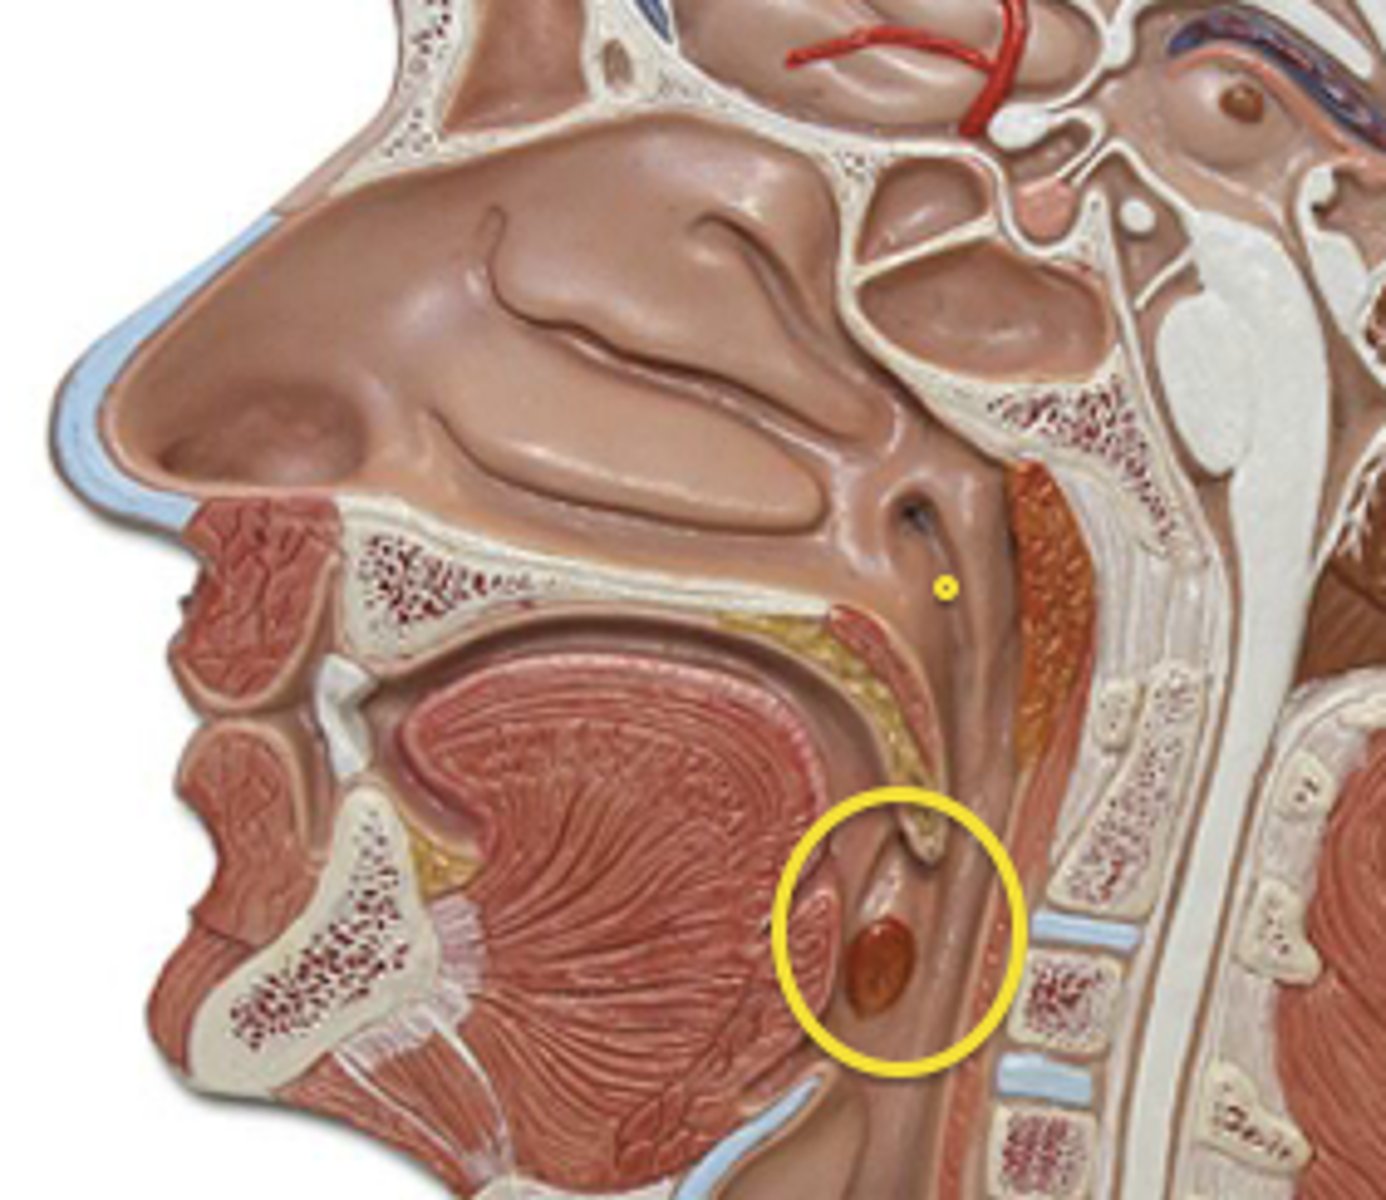

Pharynx

The membrane-lined cavity behind the nose and mouth, connecting them to the esophagus.

Nasopharynx

Region of the pharynx at the back of the nose and above the soft palate

Pharyngeal Orifice of Pharyngotympanic Tube

The base of the cartilaginous portion of the auditory tube

Oropharynx

Central portion of the pharynx between the roof of the mouth and the upper edge of the epiglottis

Laryngopharynx

Lower part of the pharynx, just below the oropharyngeal opening into the larynx and esophagus

Larynx

Voice box; passageway for air moving from pharynx to trachea; contains vocal cords

Epiglottis

A flap of cartilage at the root of the tongue, which is depressed during swallowing to cover the opening of the windpipe